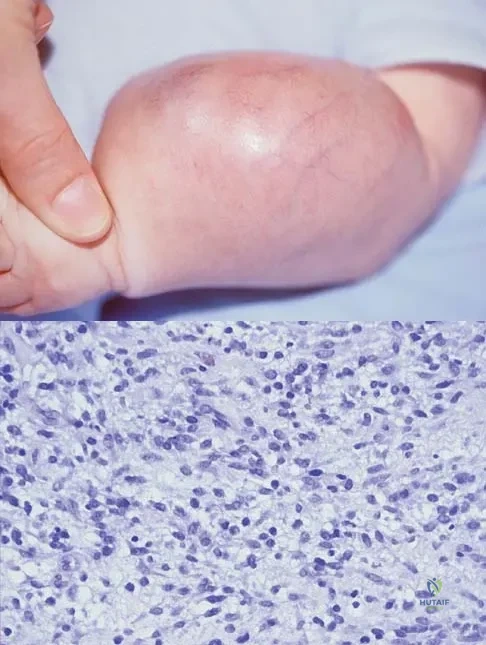

Question 84

An infant is born with a mass that involves both the volar and dorsal compartments of the left arm. A clinical photograph and biopsy specimen are shown in Figures 41a and 41b. What is the best initial course of action?

Explanation